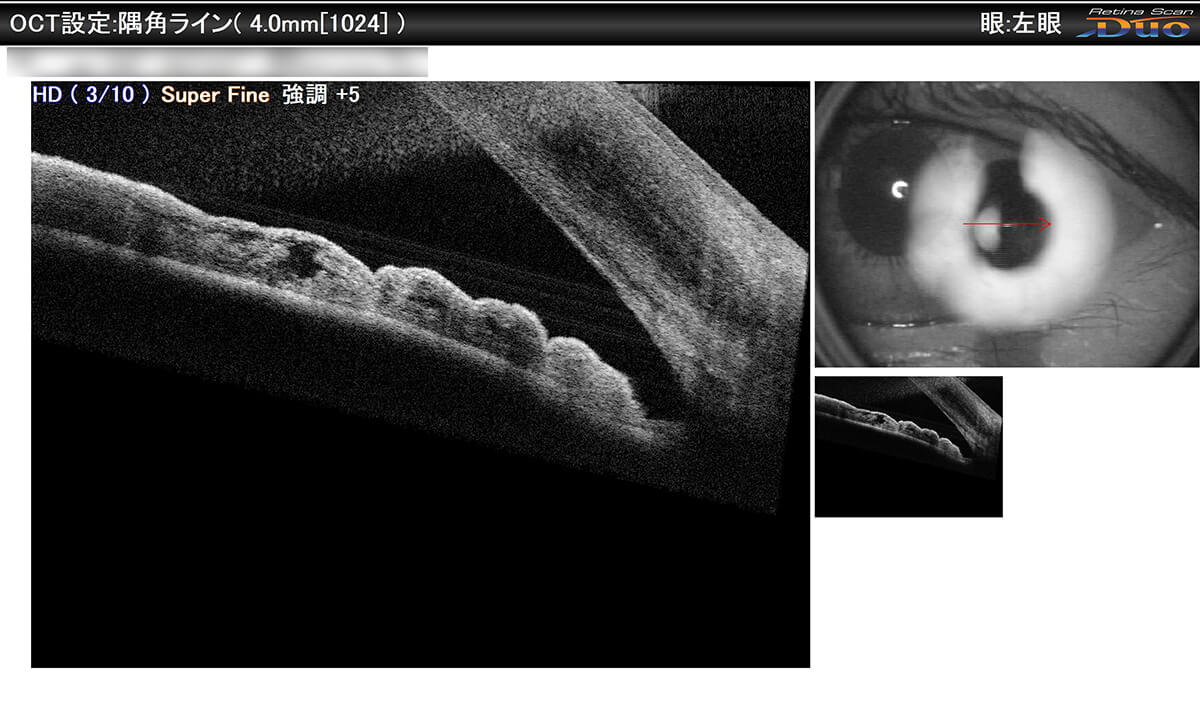

- 前眼部OCT(眼球の前の方を観察)

- 前眼部OCTは、これまでの眼科的検査では行えなかった、角膜、隅角、虹彩などの断層面の観察や立体構造の数値的解析ができる唯一の検査方法です。これにより閉塞隅角緑内障、角膜疾患(円錐角膜、不正乱視)、水晶体疾患など多くの前眼部疾患の診断・治療に大きく役立ちます。

対象疾患:緑内障・角膜疾患(不正乱視、円錐角膜)・水晶体疾患 など

- OCT隅角撮影

- 眼の中のお水(房水)が眼外排出される部分を撮影できます。これにより自覚書状のない緑内障の早期発見・治療が可能となります。

OCT隅角撮影 緑内障の危険がある隅角

狭隅角眼または閉塞隅角緑内障。房水排出部が閉塞し、今後緑内障発作の危険があるため、レーザー治療が必要です。

OCT隅角撮影 狭隅角眼

緑内障の危険性があるためレーザーによる治療を行いました。